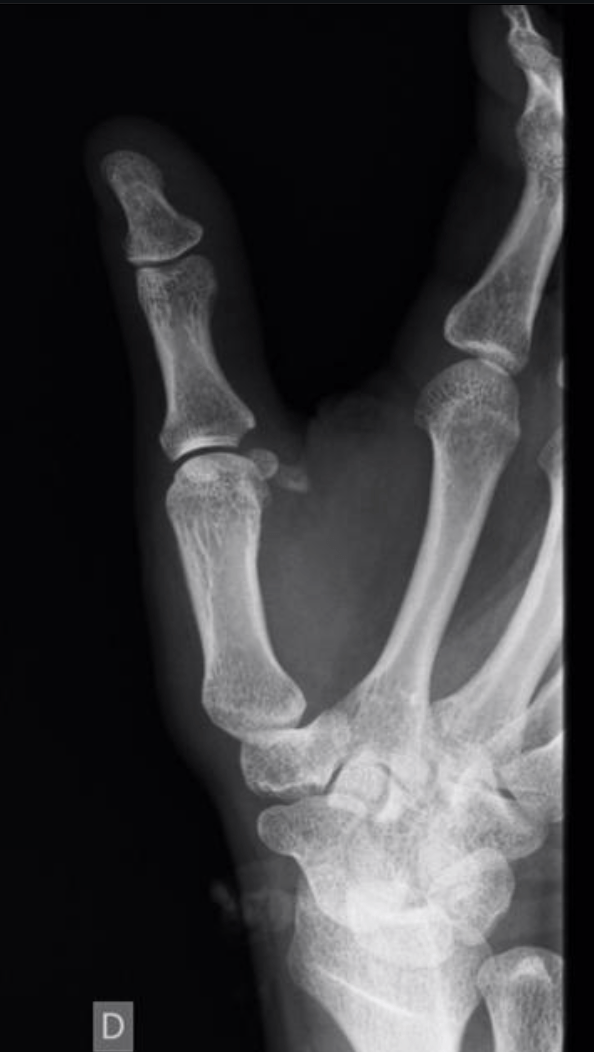

Fall onto his right hand, with pressure on the thumb and index fingers resulting in metacarpophalangeal pain, swelling and functional limitation.

What is the best next step?

What is MRI to assess for Stener lesion.

BONUS: what is this lesion?